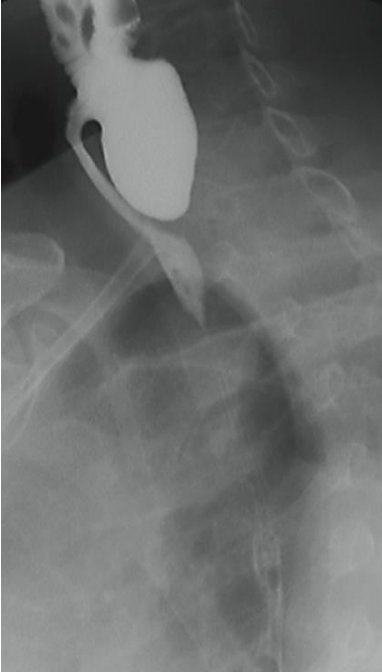

Imagem de um esofagograma em incidência lateral oblíqua evidencia a seguinte imagem, que corresponde a:

Provas